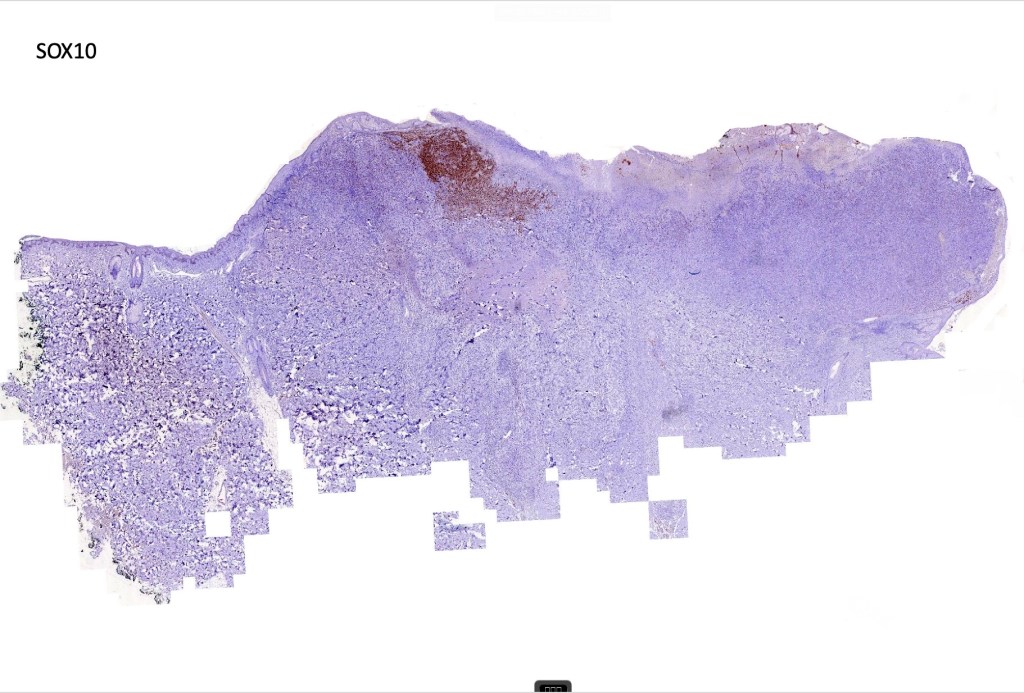

These are very rare variants of amelanotic or virtually amelanotic melanoma where a primary melanoma or a metastasis shows partial (DN) or complete loss (UN) of recognizable histological and immunohistochemical features. The histology may lead the pathologists to consider lymphoma, sarcoma, anaplastic carcinoma or a small cell tumor. Some examples of rhabdoid melanoma & melanoma with heterologous differentiation probably belong in this category. Ultimately, if there is no identifiable/recognizable primary tumor, diagnosis may only be comfortably made with next-generation sequencing. In the cases presented below, immunohistochemistry was of value in determining the melanoctic nature of the tumor (undifferentiated melanoma).